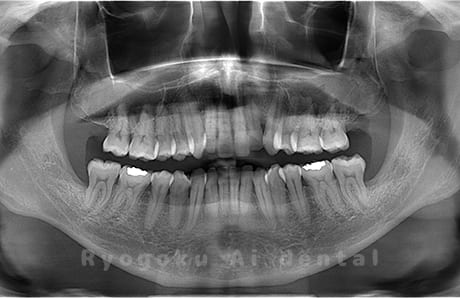

Case02

-

- 原因

- 下顎の水平埋伏智歯

- 治療内容

- 下顎の水平埋伏智歯を抜歯

<リスク・副作用>

手術後は痛み、腫れ、痺れなどの副作用が生じる場合があります。